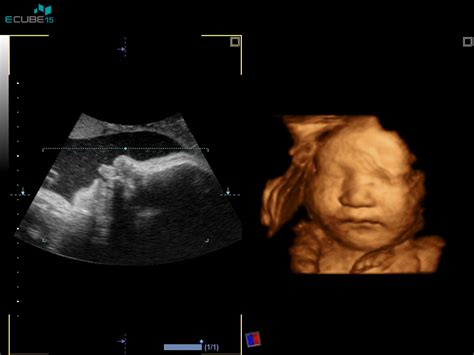

V 19. tednu plod meri 17,8 cm in tehta 200 g. V tem tednu se razvija verniks (beli, mastni, sirasti premaz), ki ščiti plod. Vsa čutila se intenzivno razvijajo. Pojavi se lahko bolečina krožne vezi, ki podpira maternico. V 20. tednu plod meri 19,7 cm in tehta 260 g. Notranji organi so že na svojem mestu kot pri odraslem, zato je čas za morfologijo, ultrazvočno oceno pravilnega razvoja ploda. Telo nosečnice se pri tem pregledu oceni lego posteljice in rast otroka.